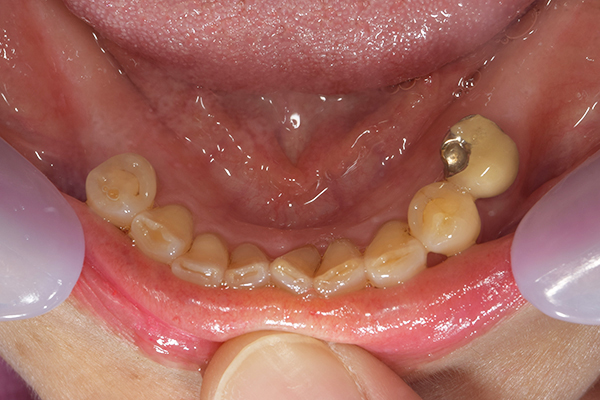

上下の入れ歯が外れやすくなったということでいらっしゃいました。 顎の骨はしっかりしていましたので、精密な型取りさえすればしっかりした入れ歯がつくれると思いました。 また下には6本歯が残っていましたが、虫歯になっている歯もありました。 かぶせ物のなかで大きな虫歯があった歯があり、1本だけ残せない状態でした。

上の入れ歯は確かに吸着は甘くなっていました。 また下の入れ歯はバネの一部が壊れており、安定感がなくなっていました。

精密な型取りの後、噛み合わせのチェックをしていきました。 かぶせ物も同時に作っていきました。

歯を並べた後、かぶせ物のフレーム作ってもらいました。先に歯を並べて理想の位置を決めておくことが大切です。

完成した入れ歯とかぶせ物です。 入れ歯への寛容度が高い患者様でしたので、 金属は使用せず、プラスチックのみで上は仕上げました。 下顎も歯は1本減ってしまいましたが、しっかり 入れ歯が維持できる様な構造にしました。

お口の中に入れた状態です。 見た目も最初とほとんど変わることなく作成できました。 維持や吸着に関しても問題ないようでした。